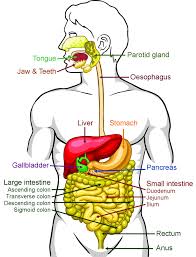

The digestive tract is a twisting tube about 30 feet long. It starts at the mouth and ends at the anus. In between are the esophagus, stomach and bowels (intestines).  The liver and pancreas aid digestion by producing bile and pancreatic juices which travel to the intestines. The gallbladder stores bile until the body needs it for digestion.

The liver and pancreas aid digestion by producing bile and pancreatic juices which travel to the intestines. The gallbladder stores bile until the body needs it for digestion.

The digestive system breaks down food and fluids into much smaller nutrients. In this complex process, blood carries the nutrients throughout the body to nourish cells and provide energy. The GI tract is divided into two main sections: the upper GI tract and the lower GI tract.